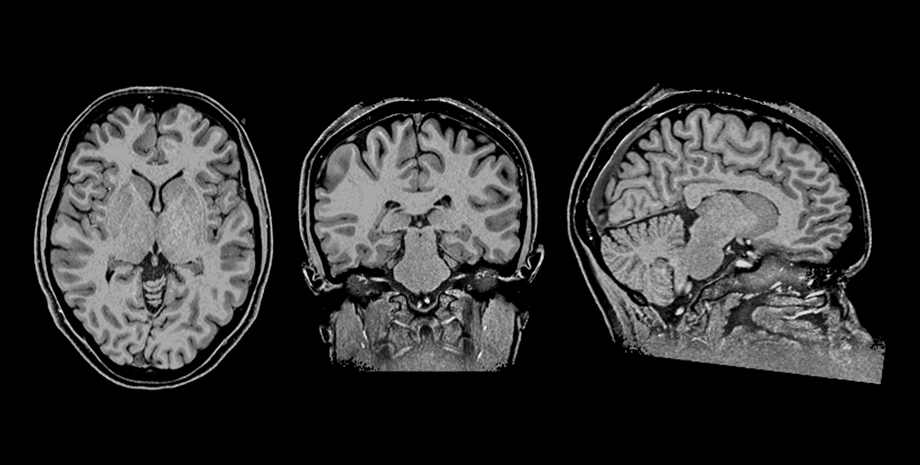

ニューロフィードバック実験中に測定された被験者のMRI画像

柴田 ニューロフィードバックではそれが可能です。まず被験者に脳活動を測るMRIに入ってもらいます。視覚野でも運動野でも、もっと抽象的な情報を扱う前頭前野でも良いのですが、ある脳領域をターゲットに設定し、その脳領域の活動を反映した信号をMRIで測定する。そうすると、安静時のベースラインよりも今は脳活動が上がったとか、下がったというデータを数秒ごとに計測できる。そのデータをリアルタイムで被験者に見せて報告する、つまりフィードバックします。例えば「あなたの脳の後ろの方にある視覚野の活動は、何もしてないときよりも、今はこのぐらい高いですよ」とか「ちょっと下がりました」とか、その場で被験者に情報をフィードバックしていく。そうすると被験者は、「上げてください」と言われたら上げられたりと、自分で自分の脳活動パターンを変化させられるようになるんです。